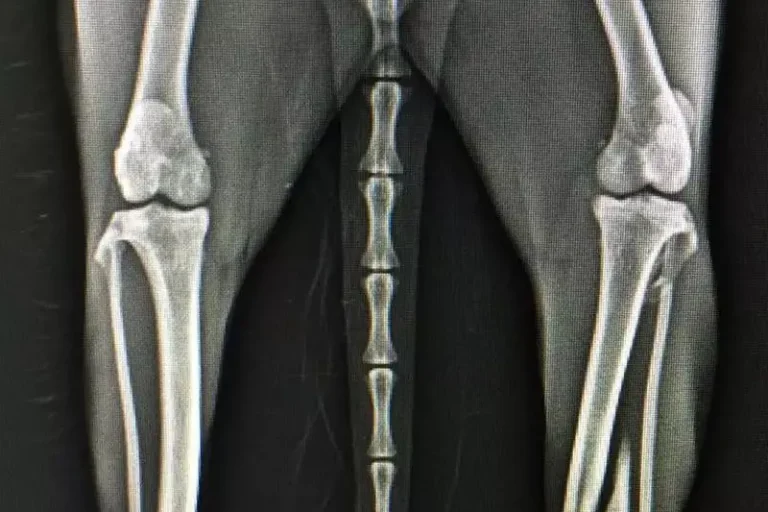

Evcil hayvanlar, yaşamları boyunca çeşitli ortopedik sorunlar yaşayabilirler. Bunlar arasında kırıklar, çıkıklar, eklem problemleri, kemik tümörleri ve kalça displazisi gibi rahatsızlıklar yer almaktadır. Bu…

VERSİYON 1 İlgi Hayvan Hastanesi, evcil hayvanların iskelet ve kas sistemleriyle ilgili çeşitli tıbbi problemleri çözmek için uzman bir cerrahi ekibe sahiptir. İskelet ve…